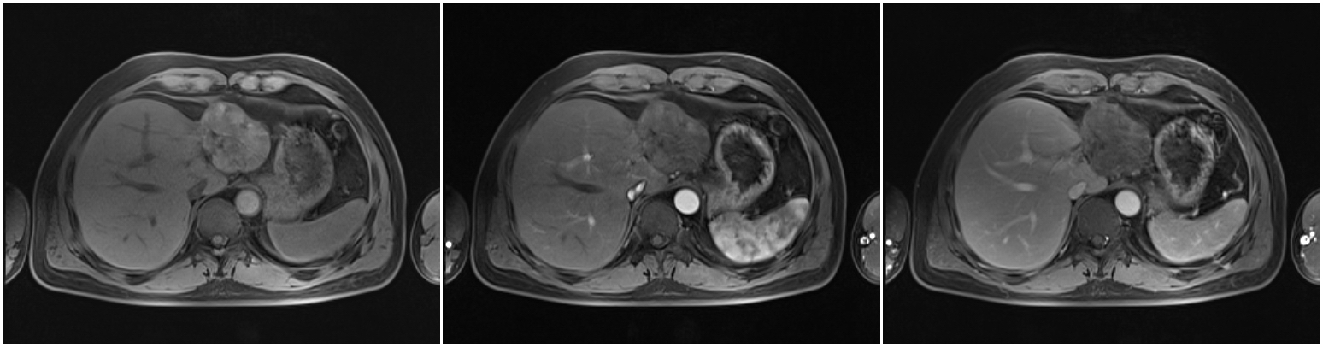

2011-01-06我院上腹部CT:

肝左叶巨块型肝癌(13.8cm×9.1cm),伴肝右后叶子灶,门静脉左支、肝左静脉及下腔静脉内癌栓。

2011-01-07 对肝左叶病灶行第1次TACE术(碘化油18ml,THP 46mg)

2011-02-12复查CT示:肝左叶碘油散在沉积,病灶大部分仍有活性,肝右后叶病灶未见碘油沉积;门静脉癌栓较前进展,累及主干及右支;肝左静脉及下腔静脉内癌栓无明显变化。AFP:26802 ng/ml。

2011-02-16行第2次TACE术(碘化油15ml,THP 45mg)

2011-04-20复查CT示:肝左叶病灶较前缩小,肝右叶病灶见碘油致密沉积;门脉癌栓左支较前缩小,右支癌栓消失;下腔静脉、肝左静脉癌栓消失。AFP:4983 ng/ml。